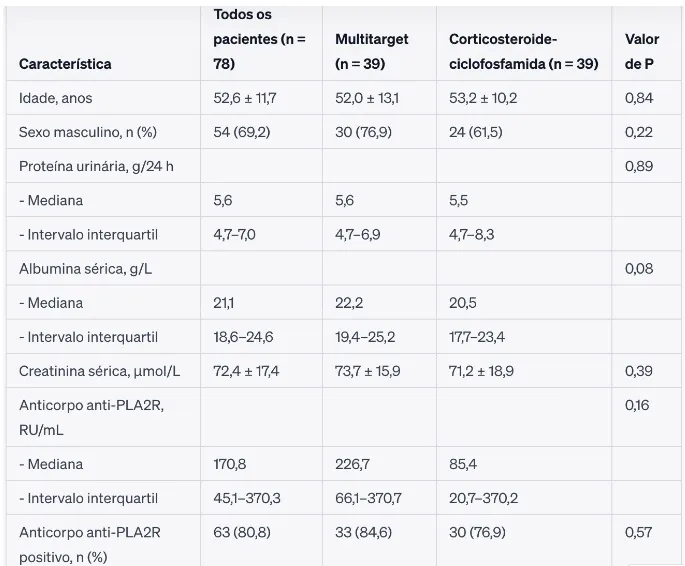

Foram randomizados 78 pacientes (39 para cada grupo). A tabela abaixo apresenta as características de base dos pacientes.